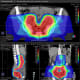

Case 2 | RECURRENT ENDOMETRIAL CANCER IN PARAAORTIC NODE

Patient Case

Patient is a 76-year-old woman with a hx of breast ca and stage IIIC1 high grade uterine carcinosarcoma initially diagnosed in 2013 treated with total abdominal hysterectomy, bilateral salpingo-oopherectomy, and lymph node dissection. Pathology demonstrated <50% myometrial invasion, lymphovascular space invasion and evidence of 6/6 involved right pelvic lymph nodes and 2/5 involved left pelvic lymph nodes). She went on to receive 6 cycles of chemotherapy followed by external beam radiation with intensity modulated radiation therapy (IMRT) to 45 Gy and vaginal brachytherapy 7 Gy x 3. She then had a biopsy proven recurrence in a para-aortic node 4 years later.

Treatment

She was treated with proton therapy due to prior radiation to reduce dose to organs at risk.

Proton Plan: Isodose, Dose volume histogram, Dose Statistic